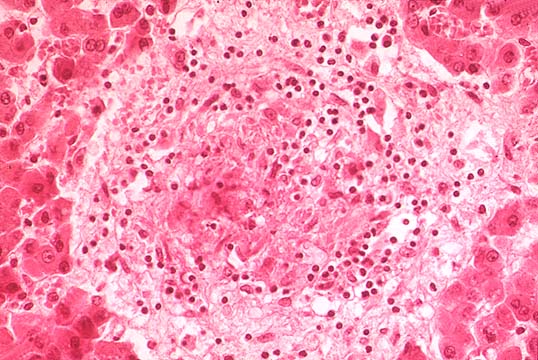

Same granuloma

Fig.139-Same granuloma

with acid-fast stain. The acid-fast organisms, red, are agglomerated inside histiocytes.